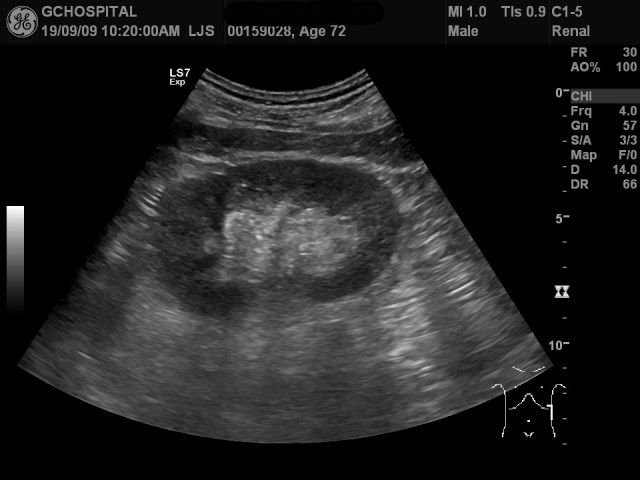

72세 여자 환자분이 우측 복통을 호소해서 촬영한 초음파영상입니다. 지방간으로 간실질의 에코가 증가해 있습니다. 오른쪽 콩팥에 형태이상이 결석과 같은 이상소견은 보이지 않으나, 신수질과 피질간의 경계가 뚜렷하게 확인이 되지 않습니다.

신피질과 수질간 경계면이 확실치 않은 경우에는 반드시 신장에 이상소견의 가능성을 염두에 두고 끝까지 확인하는 자세가 필요합니다. 이 환자분의 경우에도 간초음파만 나온 상태이지만, 추가로 엎드린 자세에서 탐촉자를 등쪽으로 접근해서 우측 신장과 탐촉자 사이의 거리를 줄이고, dynamic range와 gain 값을 세심하게 맞추어서 다시 영상을 얻었더니, 신피질과 수질의 에코음영 차이가 정상보다 훨씬 뚜렷하게 나있는걸 발견했습니다.

우측 신장의 신피질 에코음영이 정상보다 더 증가한 경우이며, 신장에 문제가 생긴 것임을 확인한 것입니다.